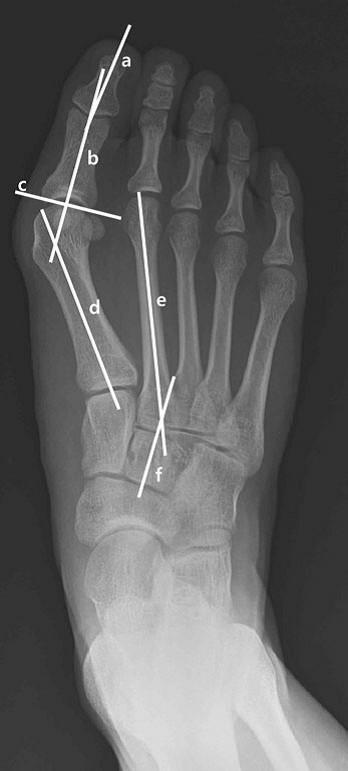

(A)拇外翻角和(B)第1-2跖骨角的测量可以反映拇外翻畸形的严重程度。

拇外翻角:第一跖骨轴与第一近端指骨轴之间。

x线片通过观察第一跖骨和近节趾骨的中轴线之间形成的角度来确定拇外翻的存在。如果角度大于15度,则诊断为拇外翻。45-50°的角度被认为是严重的。同时还应考虑第一节MTP关节内的籽骨移位程度和骨关节炎程度的变化。

在纵向将近节指骨和第一跖骨中轴线之间形成的角度称为拇外翻角(hallux valgus angle,HVA)。小于15°视为正常。大于等于20°的角度视为异常。45-50°的角度被认为是严重的。